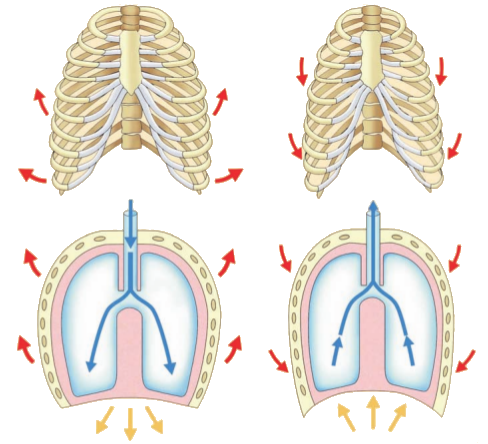

La respirazione meccanica

Si denomina così il processo ciclico che mantiene costante la quantità di aria nei polmoni. Comporta due fasi: la inspirazione, che introduce l'aria atmosferica nei polmoni e la espirazione che la espelle. Per queste funzioni il sistema respiratorio conta sulle strutture annesse: il diaframma, i muscoli intercostali e i muscoli addominali sono quelli che svolgono le funzioni più importanti (vedi tabella qui sopra).

- INSPIRAZIONE: Quando inspiriamo, il diaframma e i muscoli intercostali esterni e interni si contraggono. Nella inspirazione forzata (provocata da una intensa attività fisica ed una alta esigenza respiratoria) intervengono inoltre i muscoli pettorali e gli sternocleidomastoidei.

Al contrarsi del diaframma, il suo centro scende verso il basso, il che produce un aumento verticale della cavità toracica, spingendo i visceri addominali verso il basso. La contrazione dei muscoli intercostali produce l'elevazione delle costole e la spinta in avanti dello sterno. In questo modo i diametri anteroposteriore e laterale aumentano, causando un aumento del volume polmonare. Questo aumento causa un vuoto che causa una differenza di pressione con la pressione atmosferica. In questo modo l'aria atmosferica entra per creare un equilibrio. - ESPIRAZIONE: Si produce quando il diaframma e i muscoli intercostali si rilassano (tornano alla loro posizione abituale). Questo significa che il diaframma si alza e i muscoli intercostali discendono, diminuendo il volume della cassa toracica, quindi dei polmoni stessi. La diminuzione del volume polmonare causa un aumento di pressione nei polmoni che porta l'aria ad uscire. Contribuiscono alla espirazione anche i muscoli addominali, che comprimono la cavità addominale spingendo i visceri verso l'alto contro il diaframma.